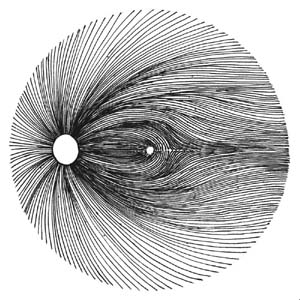

Buňky v centrální části sítnice se začínají diferencovat nejdříve a již za týden jejich výběžky dosahují až k terči. Tak vzniká základ makulopapilárního svazku. Během dalších několika dnů se diferencují gangliové buňky v perifernějších oblastech sítnice. Těm, které rostou z temporální strany, překáží v cestě ke zrakovému nervu již vytvořený makulopapilární svazek a musí jej obloukovitě obejít. Vlákna rostoucí z gangliových buněk z nasální strany takovou překážku na cestě nemají a jejich průběh ke zrakovému je přímý. Tímto způsobem během několika dní vzniká vrstva nervových vláken. Její uspořádání nám umožňuje pochopit lokalizaci skotomů zorného pole.

Je tvořena axony gangliových buněk pokrytých astrocyty, probíhajících v kanálcích z výběžků Mullerových buněk ve svazečcích o průměru 20 um. Svazečky jsou morfologickým podkladem jemného žíhání. Světlé proužky mezi tmavými mezerami jsou výběžky Mullerových buněk, ve kterých probíhají nervová vlákna. Temporálně i nasálně je žíhání jemné a každý proužek je tvořen jedním svazečkem vláken. V horním i dolním temporálním kvadrantu je jsou proužky silnější a tím i lépe viditelné, každý proužek má několik svazečků (svazečky jsou v několika vrstvách).

Při progresi glaukomu nejprve bývají poškozeny gangliové buňky v blízkosti temporálního švu sítnice. Jejich axony probíhají v hlubší vrstvě nervových vláken a do zrakového nervu pronikají v jeho periferii. Protože vzniklý defekt je překryt dalšími povrchnějšími vrstvami, výpadek není při pozorování sítnice zřetelný. Až po ztrátě poloviny vrstvy nervových vláken se defekt stává zřetelným oftalmoskopicky.